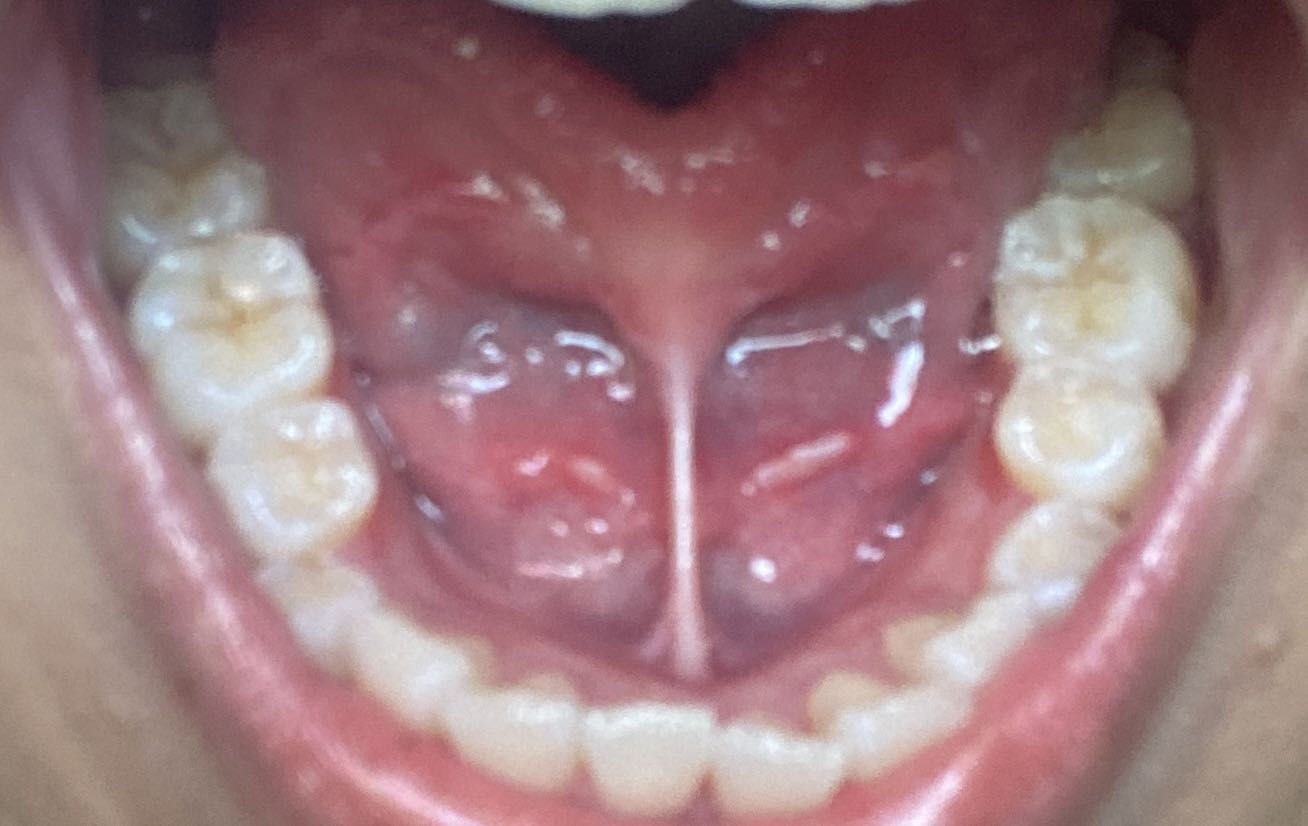

บริเวณใต้ลิ้นมีติ่งแบบนี้ขึ้นมาคืออะไรคะ

สวัสดีค่ะ ขอสอบถาม คือว่าใต้ลิ้นของเรามีมีติ่งเนื้อแบบนี้ขึ้นมาค่ะ

-ก่อนหน้านี้เราเป็นเริมที่ปาก *ไม่เคยมีเพศสัมพันธ์*

ได้ทำการกินยาฆ่าเชื้อที่ซื้อโดยเภสัช และรู้สึกเจ็บที่ใต้ลิ้นมากค่ะเวลาทานของเผ็ด พอส่องกระจกแล้วเห็นเป็นติ่งเนื้อแบบนี้ก็ตกใจมากเพราะไม่เคยเป็นมาก่อนค่ะ

-เป็นมาราว1 อาทิตย์แล้วค่ะ